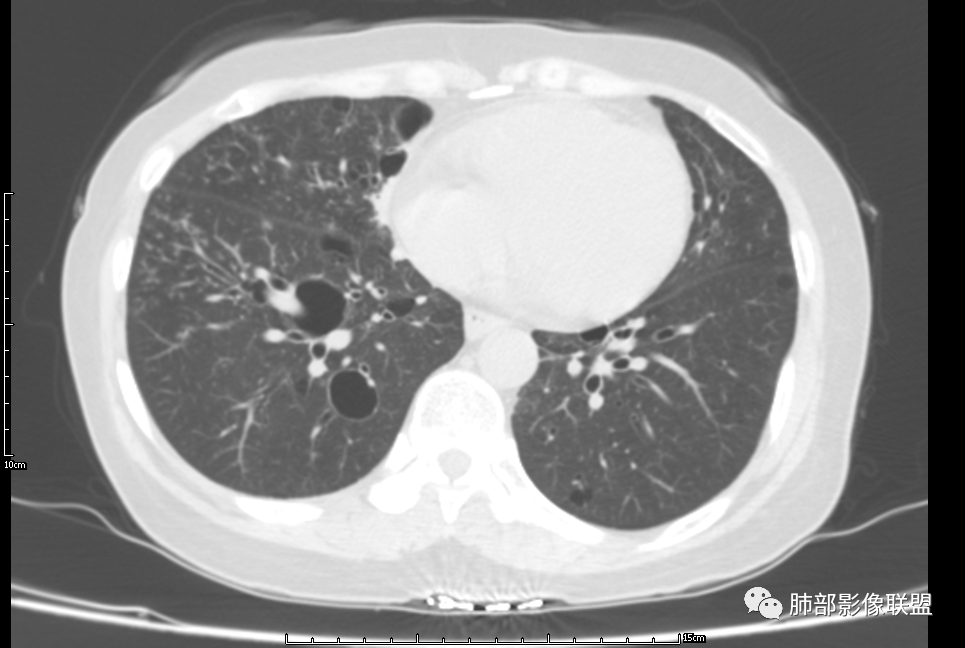

CT平扫示双肺弥漫分布大小不等囊状薄壁透光区,无内、中、外带分布差异,间质稍示增厚。拟LAM

中年女性育龄期妇女,咳嗽气喘,无吸烟史,有苯吸入史。影像:双肺弥漫均匀小囊腔,无明显分布优势,囊腔形态欠规则,壁薄,部分囊腔边缘血管征,伴双肺弥漫磨玻璃影,无结节,考虑lam,鉴别苯中毒肺损伤,囊腔多有分布优势,小叶中心分布为主,形态规整等

女,46,活动性气喘1年。苯吸入史半年。胸部CT:两肺弥漫囊腔,上至肺尖,下至肋膈角,形态类似小囊腔。考虑:LAM,鉴别LIP,BHD,PLCH等。

双肺弥漫大小不一薄壁含气囊腔,囊间肺组织正常,正常肺背景,肺尖肺底受累;青年女性,气喘,支持LAM

双肺多发大小相近的囊状影,分布趋势趋于一致,中年女性,考虑LAM。部分囊内见血管及分隔影,小叶中心性肺气肿代排

CT表现:双肺弥漫大小不等的薄壁囊腔,囊壁<2mm,外形规则,血管影多位于囊腔周围,囊腔之间肺组织正常,随着疾病进展到晚期,囊腔变大、增多,不可胜数,囊腔可融合成较大的囊,与肺气肿相似,形成间质性肺纤维化。部分病例可出现结节影。

1.小叶中心性肺气肿:上肺为主,无壁,中央见小血管影,位于小叶核心周围,部分血管可推移到边缘,周围肺组织正常

CT表现:早期阶段以结节为主,小结节分布于小叶内、支气管血管束旁及小叶间隔,囊腔形态不规则,呈分支状、两叶或三叶,大小不一,囊壁厚薄不均,主要以中上肺受累为主,双侧肋膈角往往不受累,终末期过度充气及广泛囊腔形成网状纤维化或终末肺气肿,也可导致自发性气胸。